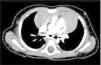

A previously healthy one-month infant was referred to our institution due to a heart murmur. The transthoracic echocardiogram showed the pulmonary trunk giving rise to the right pulmonary artery (RPA), but the left pulmonary artery (LPA) was not identified in its usual location. Instead the LPA was arising from the RPA and coursing leftward behind the trachea, with a turbulent flow (peak velocity 1.5 m/s) (Video 1). An associated ostium secundum atrial septal defect was diagnosed. The suspected diagnosis of pulmonary artery sling was confirmed by computed tomographic angiography. The LPA was seen originating from the posterior aspect of the RPA and coursing over the right mainstem bronchus and then from right to left, posterior to the trachea and anterior to the esophagus, to reach the hilum of the left lung, and causing a mild compression of the origin of the LPA (Figure 1). Besides the pulmonary artery sling and the atrial septal defect, a partial anomalous pulmonary venous return was identified, with the left superior pulmonary vein draining in the left brachiocephalic vein (Figure 2).